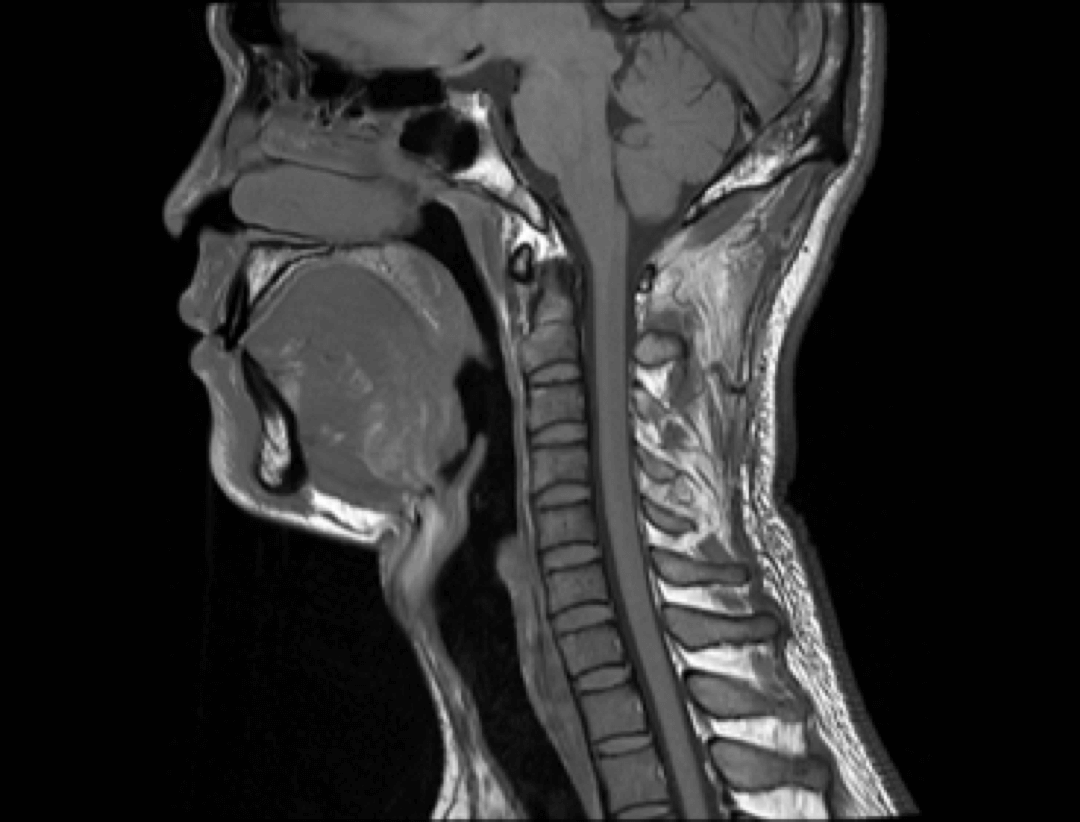

Neurologia

Kręgosłup